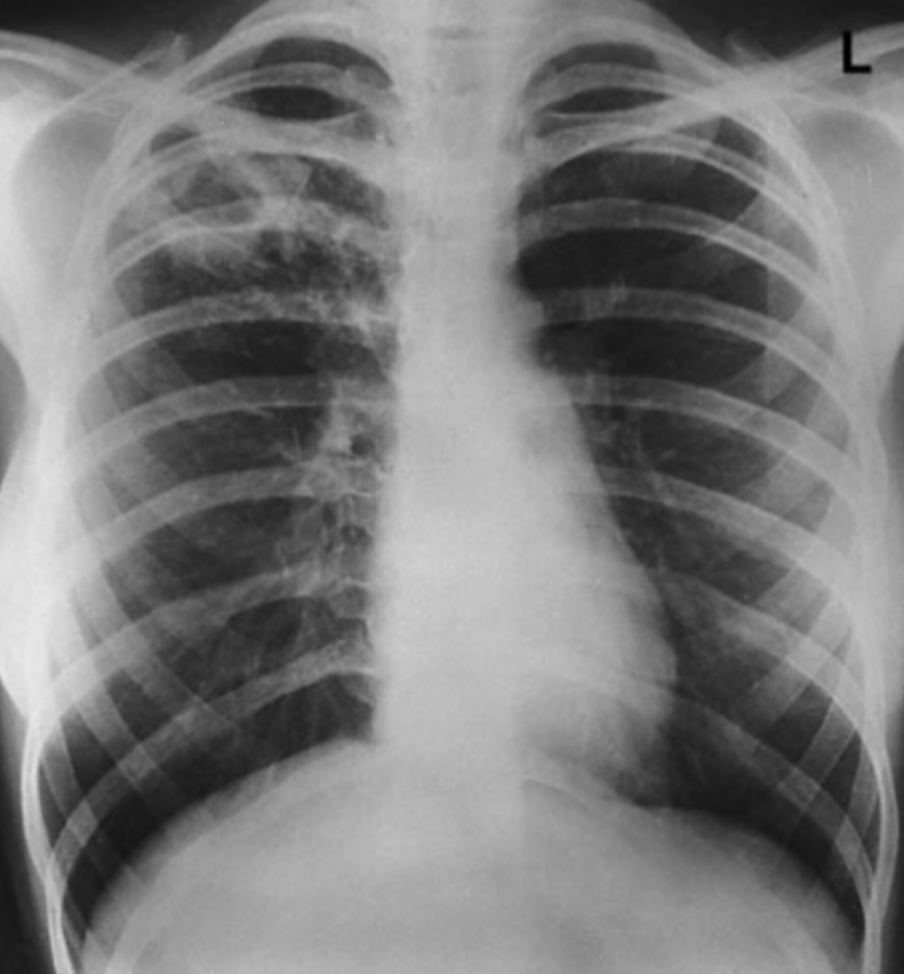

UPPER lobe infiltrate + hemoptysis/weight loss = reactivation TB Key in history: AFTER a patient was treated w/ infliximab (or other TNF-a inhibitors: etanercept, adalimumab, certolizumab bc it blocks granuloma structure) **This is ALMOST always in a patient tx for rheum dz